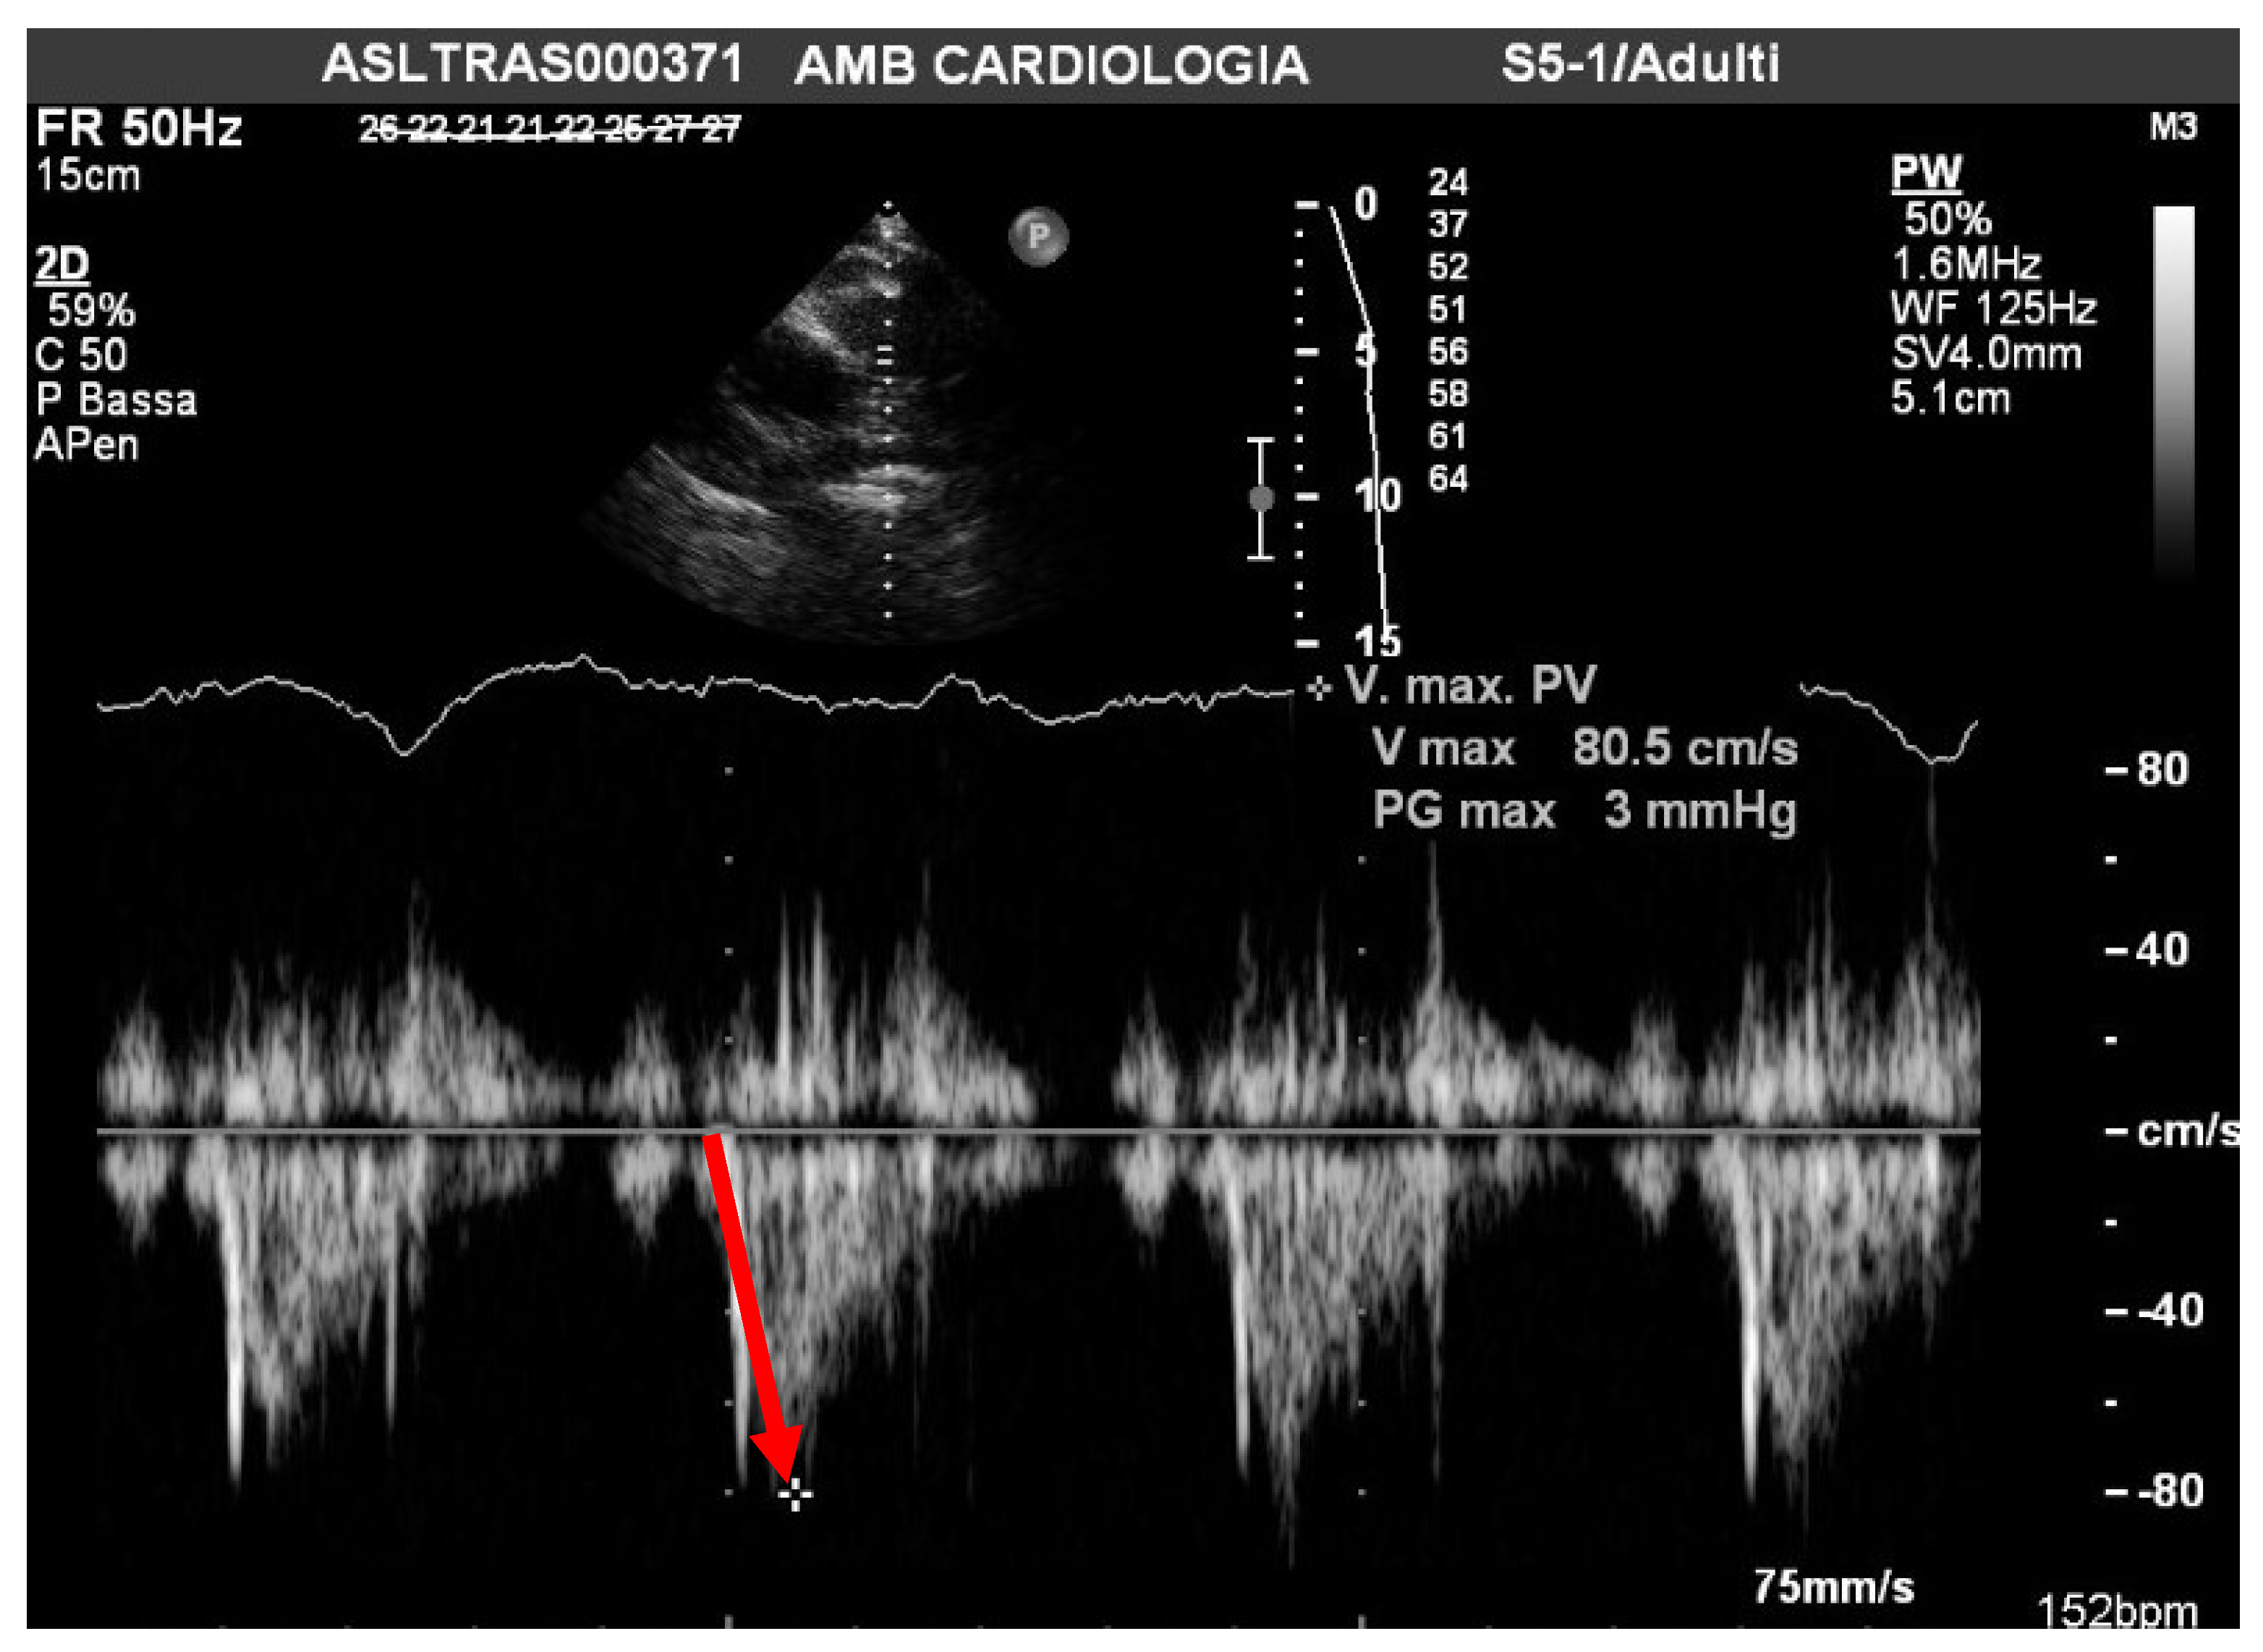

| PAAT | acceleration time of pulmonary outflow |

| sPAP/PAAT ratio | systolic pulmonary artery pressure/acceleration time of pulmonary outflow ratio |

| Mean PAAT 110 msc |

| sPAP/PAAT 0.26 |